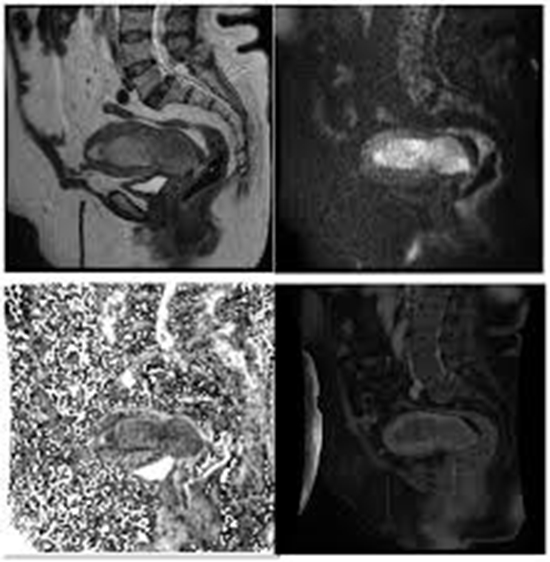

Introduction: The uterine carcinoma is the most commonly diagnosed malignancy in female pelvis. Accurate identification of tumor origin is crucial for determining appropriate treatment approaches. This study aims to develop a prediction model using multiple MRI parameters to accurately diagnose uterine cancer with an indistinctive origin and those involving both the endometrium and cervix prior to treatment. Material and methods: This prospective cohort study was conducted from January 2020 to January 2021, and included patients aged 20-80 who were newly diagnosed with uterine carcinoma who underwent MRI and were considered for hysterectomy within 6 months after MRI. Results: In our study, a total of 78 patients with uterine carcinoma were enrolled. the final diagnosis was confirmed as follows: 20 were adenocarcinoma of the cervix, 27 were SCC of the cervix, and 31 were endometrial adenocarcinoma. Certain imaging features were found to be consistent with cervical carcinoma, included parametrial invasion (69.6%), vaginal invasion (66%), stromal invasion (95.7%), and peripheral rim enhancement (68.9%). On post-contrast sequences, cervical cancer appeared hyperintense compared to the myometrium, while All rights reserved. No reuse allowed without permission. (which was not certified by peer review) is the author/funder, who has granted medRxiv a license to display the preprint in perpetuity. medRxiv preprint doi: https://doi.org/10.1101/2024.04.24.24305372; this version posted April 26, 2024. The copyright holder for this preprint NOTE: This preprint reports new research that has not been certified by peer review and should not be used to guide clinical practice. 2 endometrial cancer appeared hypointense (96.8%). Endometrial carcinoma was well diagnosed by the presence of an endometrial cavity mass (100%), deep myometrium invasion (>50%) (54.8%), and a greater size in the craniocaudal dimension compared to the transverse dimension (100%). Discussion: The study found that certain morphologic features were reliable indicators for detecting cervical carcinoma, including vaginal, stromal, and parametrial invasions, the presence of hypervascularity and peripheral rim enhancement. On the other hand, myometrial invasion and the presence of a mass in the endometrial cavity were significantly higher in endometrial carcinoma. Keywords: oncology, cervical cancer, uterine carcinoma, gynecology